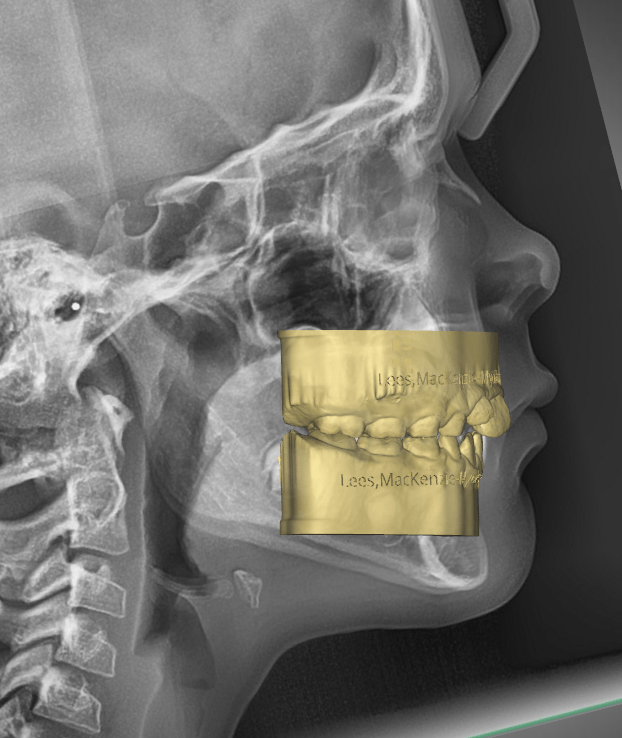

DIGITAL ORTHODONTICS

What is digital orthodontics ? For my purpose I refer to the branch of orthodontics that uses clear aligners to move teeth in a stepped sequence of movements. AKA clear aligners, aka sequential aligners ( my preference ) or as what most of you might refer to as Invisalign®. This is as opposed to the… Read.